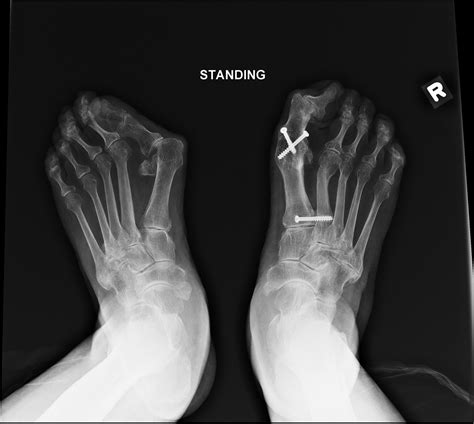

• Hallux Valgus: Also known as a bunion, this condition involves a misalignment of the big toe, causing it to angle towards the second toe. This can lead to pain, swelling, and difficulty wearing shoes.

Diagnosing problems with the 1st MTP joint typically involves a combination of physical examination, medical history, and imaging tests. A healthcare professional will assess the joint's range of motion, tenderness, and any visible deformities. Imaging tests such as X-rays, MRI, or CT scans may be used to get a clearer picture of the joint's structure and identify any underlying issues.

Imaging tests provide detailed views of the joint and surrounding structures. X-rays can show bone abnormalities, while MRI and CT scans offer more detailed images of soft tissues, ligaments, and tendons.

• Osteotomy: Realigning the bones to correct deformities and improve joint function.

• Arthrodesis: Fusing the joint to eliminate pain and improve stability, although this limits mobility.

Surgical procedures are typically followed by a period of rehabilitation, including physical therapy and gradual return to normal activities.